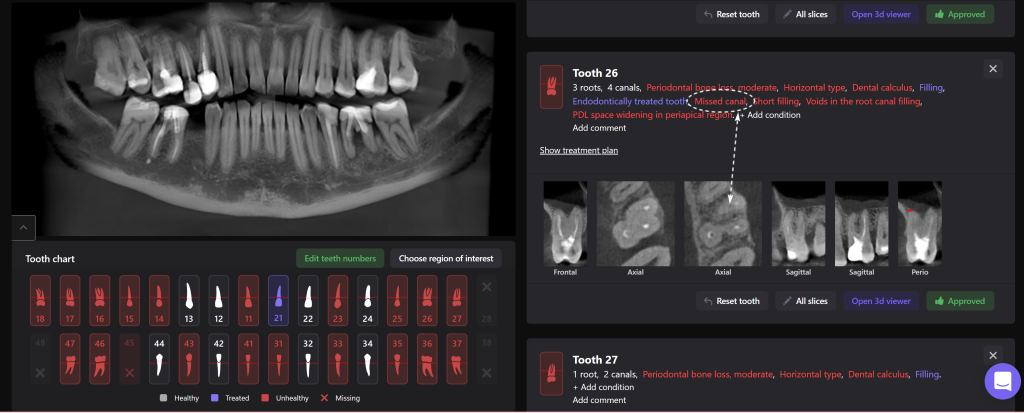

The second mesio-buccal (MB2) canal is notorious for being difficult to identify and is often left untreated, this can directly influence the outcome of the final treatment

Diagnocat AI helps us to see not only the consequences, but also the causes of the pathology. For example, in this clinical case – the missed MB2 during previous endodontic treatment of tooth 26 (Universal 14)

The 3D-Viewer allows the clinician to align the axes according to the area of interest and to study root canal morphology and anatomy before starting a treatment